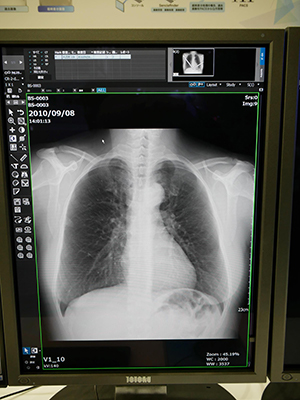

画像処理アプリケーションとして紹介された経時差分処理は,胸部X線画像の過去と今回データを自動的に位置合わせして,その変化を強調して表示する。これにより,病変部が検出しやすくなるなど,診断を支援する。比較する2つの画像の装置が異なっていても処理が可能である。また,Bone Suppression処理は,胸部の鎖骨や肋骨の信号の減弱処理を行い,目立たなくすることで,骨に隠れていた異常陰影などの見やすくした。両アプリケーションともに,病院向けPACSのNEOVISTA I-PACSシリーズに搭載できるほか,診療所向けのサービスであるinfomityでオプションとして提供される。

骨を除去して病変を見つけやすくする |

過去画像との比較を容易にする“経時差分処理”